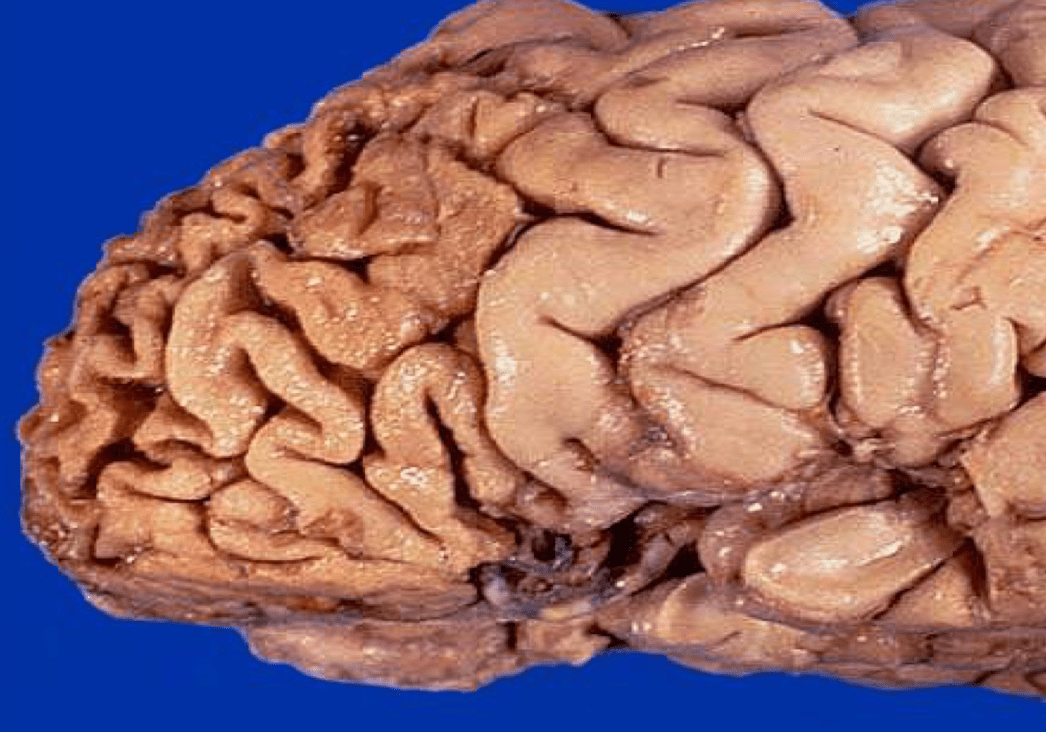

This gross brain specimen would be indicative of what kind of dementia?

What is FTD?

these are the general findings seen with frontotemporal dementia

*younger onset: 50s-60s

*there is a behavioral variant (R frontal)

*primary progressive aphasias (L frontal or L temporal)

*other tauopathies may be present (PSP, CBD)